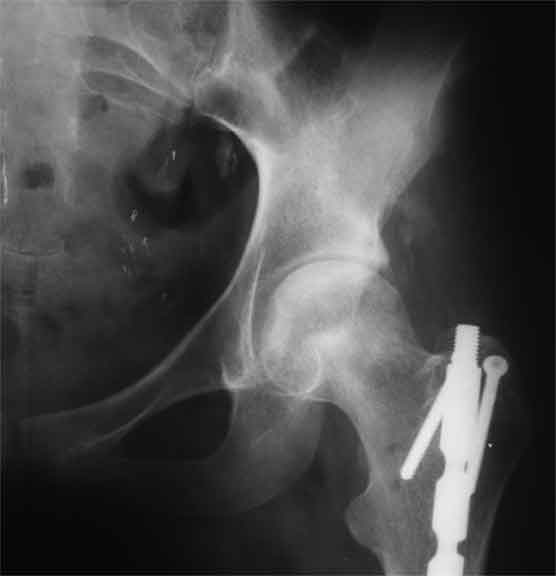

Еще пара фото, ситуация несколько иная, задачи те же, открытое вправление застарелого вывиха в 2002, молодой возраст. Сейчас госпитализирована для эндопротезирования.

Больного прооперировали на прошлой неделе (цементный протез, цемент с гентамицином). Использовали задне-боковой доступ. В области перелома подвижности практически не было, так что тему сообщения уместно заменить на "неправильно сросшаяся шейка". И в головке, и во впадине

были значительные дегенеративные изменения, так что ни биполяр, ни остеосинтез тут неуместны (хотя это предлагали в ortopod'е). После релиза удлинили ногу на 3 см. Дальше удлинять побоялись из-за

натяжения седалищного нерва, хотя в принципе можно было бы еще 15-20 мм нарастить. По послеоперационной рентгенограмме анатомическое укорочение порядка 15 мм. Клинически при ходьбе - 4 см, но это за счет перекоса таза.

The patient underwent cemented THR on last week. Postero-lateral approach was used. There was only minimal motion at the fracture site and we had to cut the femoral head with oscillating saw. The femoral head was deformed with it's cartilage completely absent in some areas.

Acetabulum showed gross degenerative changes, especially in superior rim. So I think it was right choice not to do ORIF in this case. After some soft tissue release we've lengthened the leg up to 3 cm. Further lengthening was possible but we stopped at that moment due to tension of n. ischiadicus. Now patient walks with crutches. Leg length discrepancy is about 4 cm due to pelvic tilt (discrepancy on post-op x-ray is 15 mm).